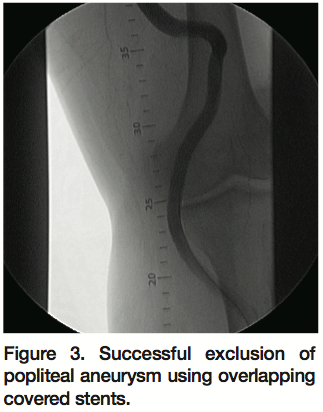

Percutaneous intervention was performed using an 8 Fr 45 cm sheath and a Glidewire (Terumo Medical Corp., Somerset, New Jersey) across the aneurysmal segment. The long and tortuous aneurysm was covered with a total of 4 Viabahn® self-expanding covered stent grafts (W. L. Gore & Associates, Flagstaff, Arizona) deployed in an overlapping fashion (7 x 100 mm, 9 x 150 mm, 11 x 100 mm, and 11 x 150 mm distal to proximal) to exclude the entire aneurysm (Figure 3). Following final stent deployment, the proximal and distal landing zones as well as the areas of overlap were postdilated at low pressure to ensure adequate stent apposition. Final angiograms revealed brisk flow with no evidence of endoleak and preserved distal runoff (Figure 4). The patient was discharged home the following day in stable condition on aspirin and reinitiation of warfarin for chronic atrial fibrillation.